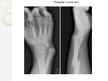

Rentgenā veic kaula lūzuma pārbaudi, novērojot kā kauls ir salūzis.

Vienkāršā lūzuma gadījumā roku iešinē vai ieliek ģipsī.

Smagākākiem lūzumiem veic operācijas, izņemot sadrupušos vai nevietā atrodošos kaulus. Ievieto metāla tapas visā kaula, metāla plāksne ar skrūvēm,skrūves bez papildu stiprinājuma elementiem,vidū kaula bārs.